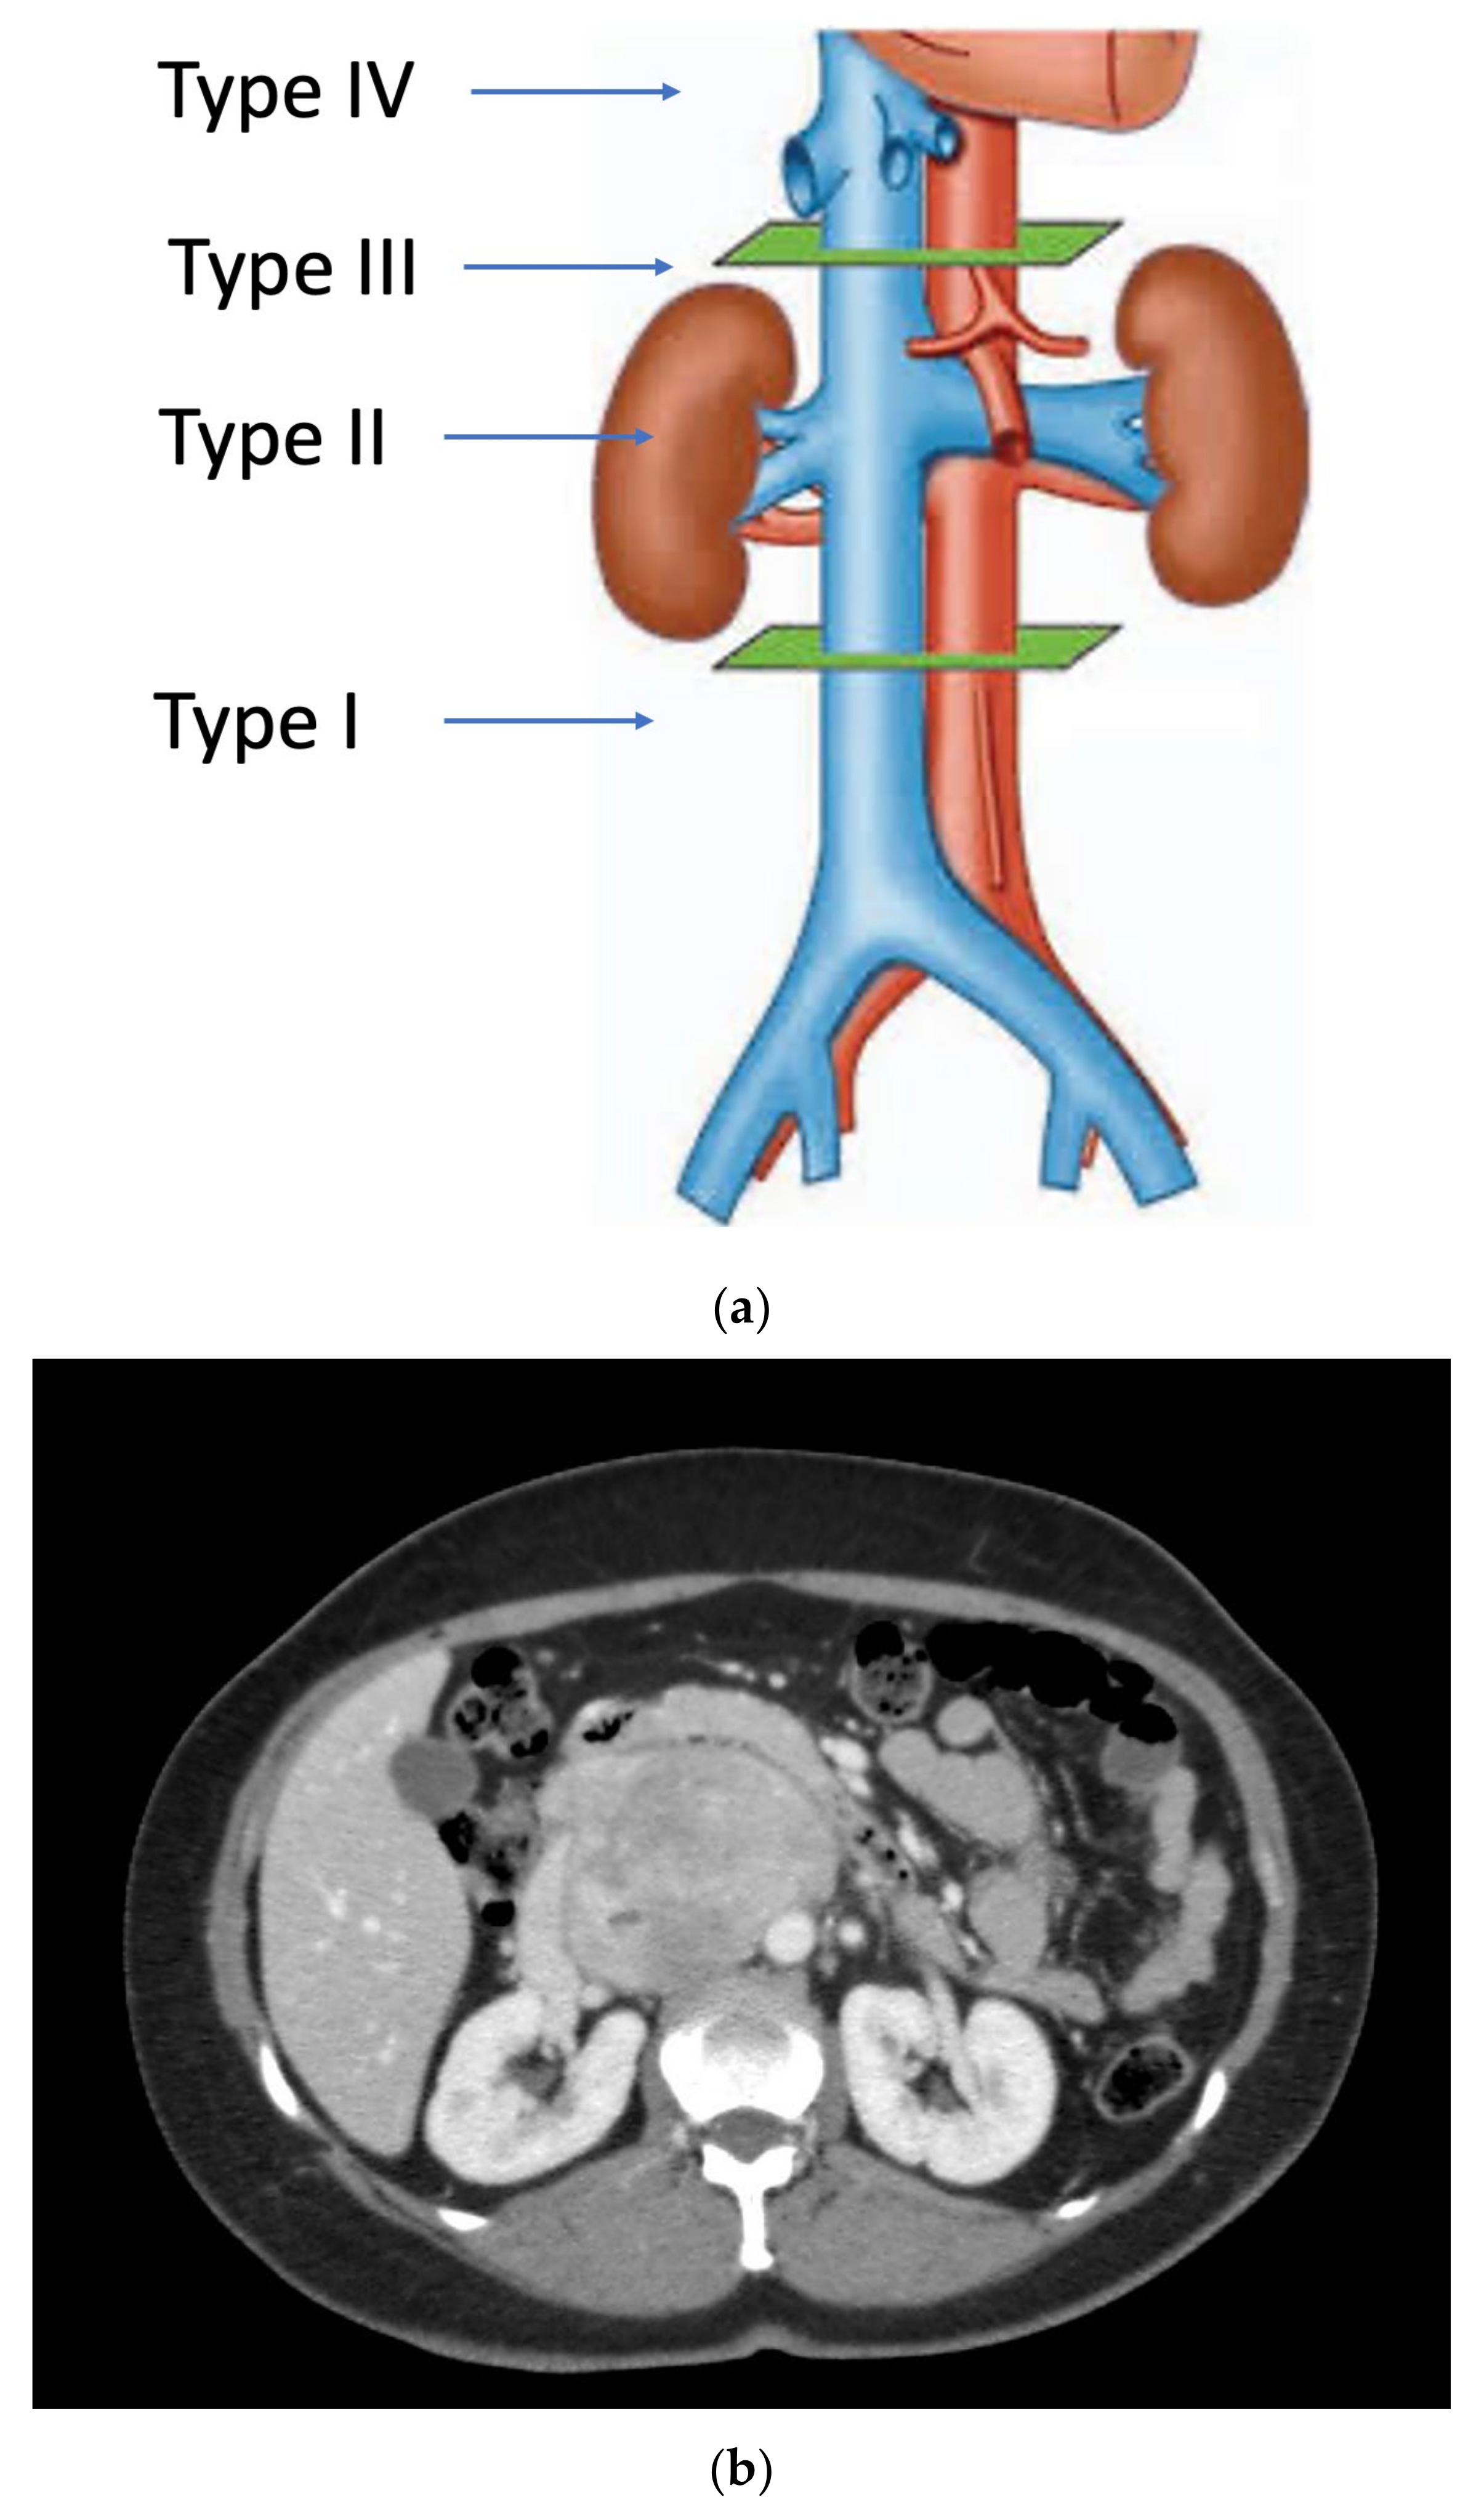

Primary vascular sarcomas of the retroperitoneum can require complex vascular reconstructions, albeit with a less extensive multi-visceral resection since they normally don’t infiltrate other surrounding organs. Primary malignant vascular sarcomas of the retroperitoneum include mainly LMSs and angiosarcomas; RP-LMSs arise from the smooth muscle layer of vasculature of the retroperitoneum with a significant proportion that develop from large blood vessels such as the vena cava, iliac, or renal veins. Caval LMSs have a slight gender predominance in women and can develop at any segment of the vena cava, from the iliac vein confluence to the right atrium of the heart. Caval LMSs can be defined following Vollmann’s classification depending on level of origin within the vena cava as type 1 (originating between the confluence of main iliac veins and below the level of renal veins), type 2 (originating at the level of renal veins), type 3 (originating above renal veins and below major hepatic veins), and type 4 (at the level of the major hepatic veins and right atrium) (Figure 1) [8,20].

As aforementioned, tumor involvement of the IVC can be defined according to Vollman’s classification (Types 1–4) (Figure 1).

Figure 1. (a) Vollmann’s IVC-LMS classification; (b) type 2 IVC-LMS.